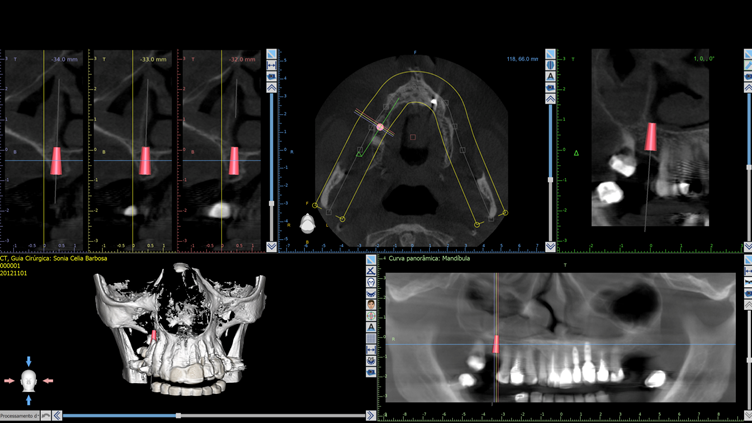

Planejamento

A paciente, de 57 anos, apresentava ausência do dente 16 e queixa mastigatória. A qualidade óssea foi estimada como tipo III (osso trabecular moderadamente denso) e, diante do biotipo periodontal favorável (gengiva espessa), optou-se pelo implante Cone Morse Maestro Superiore 4,0 × 0,9 mm. Sua macrogeometria favorece a formação óssea inicial e otimiza a estabilidade mesmo em osso de densidade moderada, permitindo alto torque de inserção sem compactação excessiva graças às câmaras de cicatrização que aliviam a pressão interna.

No planejamento protético, definiu-se o uso de um pilar Ideale 4,5 × 4 mm, rotacionalmente livre, que permite instalação em qualquer posição e pode receber coroas cimentadas ou parafusadas. A escolha visava otimizar a resposta tecidual e oferecer flexibilidade restauradora. Optou-se por coroa unitária parafusada diretamente ao pilar, confeccionada em zircônia monolítica pela sua durabilidade e estética. O fluxo seria totalmente digital: após a osseointegração, o pilar seria escaneado com scan body específico e a coroa desenhada virtualmente para fresagem em zircônia de alta resistência.